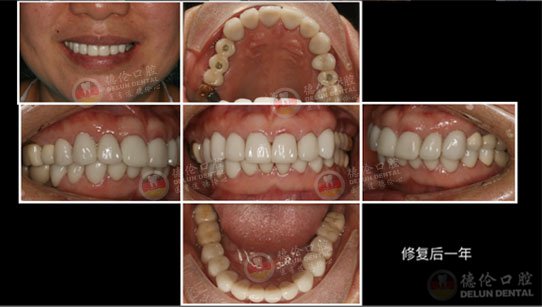

李医生诊疗案例